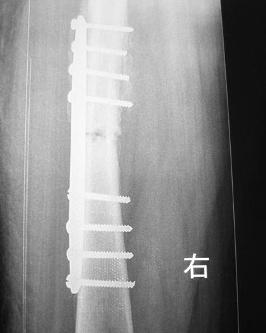

♥股骨髁上骨折

股骨髁上骨折指发生于腓肠肌起始点上2~4cm范围内的骨折。多发生于青壮年患者。不应包括内外髁部骨折和髁间骨折(AO股骨远端A型骨折)髁上骨折一般为关节囊外骨折,而髁部骨折(股骨远端B型骨折)及髁间骨折为关节囊内骨折但髁上骨折与髁间骨折常相互波及又称经髁间的髁上骨折或股骨远端C型骨折。